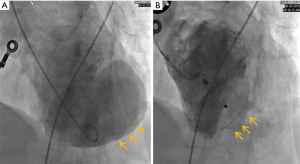

A 66-year-old woman was admitted to our center on June 2, 2018 with a confirmed diagnosis of AMI. She had undergone mitral valve replacement with St. Jude Medical E100-29M biological valve in 2012 due to mitral valve prolapse syndrome and severe mitral incompetence. Coronary angiography performed on the second day after her admission showed that the distal left circumflex coronary artery was completely occluded. Since the vessel was tine, no stent was implanted. Echocardiography revealed the presence of LVFWR and pseudoventricular aneurysm. Cardiac magnetic resonance imaging (MRI) performed on May 10 and May 31, 2018, revealed a giant pseudoventricular aneurysm located in the inferior and lateral walls of the left ventricle; the rupture diameter increased from 22 to 28 mm, and the maximum tumor diameter increased from 40.9 to 90.2 mm (Figure 1A,B). The patient developed discomforts such as orthopnea and anorexia, along with worsening symptoms. Blood biochemical tests showed her NT-proBNP was >35,000 pg/mL. Since the patient had become critically ill and her heart rupture had lasted 4 weeks, transcatheter closure under general anesthesia was performed on June 5. An incision was made to expose the left carotid artery (CA), and left heart ventricular angiography performed through the CA revealed the presence of a giant pseudoventricular aneurysm. The diameter of the rupture at the ventricle was about 30 mm. A CA-ascending aorta-left ventricle-pseudoventricular aneurysm track was established, and a 36-mm atrial septal occlusion device (SHSMA, Shanghai, China) was successfully placed. Left ventricular (LV) angiography and cardiac ultrasound were performed immediately after operation. It was found that the occlusion device was fixed to the LVFWR, and there was only a small number of residual shunts in the pseudoventricular aneurysm (Figure 2A,B).